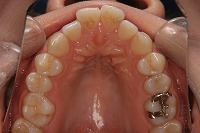

上顎

25歳6ヵ月